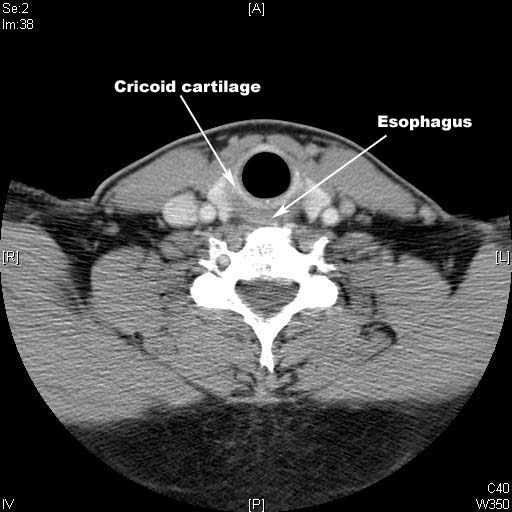

Identify Cricoid cartilage